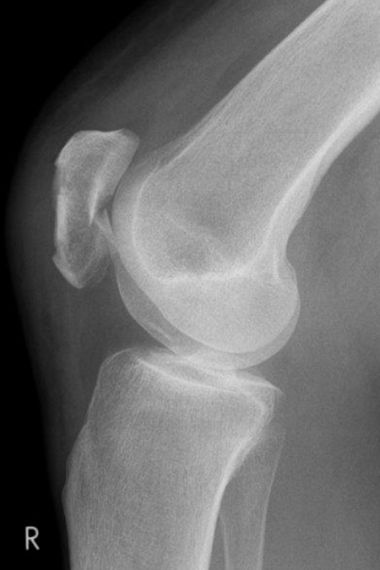

Bild Patientin 3 Monate nach Tibiakopffraktur

„Ich bin an einem Sonntag mit meinem Fahrrad gestürzt und dachte zuerst gar nicht, dass das so schlimm gewesen ist. Der Schienenbeinkopf war jedoch auf der Außenseite gebrochen und die Gelenkfläche richtig eingedrückt. Das konnte man auf den CT- Bildern gut sehen. Nach der Operation habe ich dann eine ganze Zeit entlastet aber schon bewegt. Jetzt 3 Monate nach der Verletzung geht es eigentlich schon ganz gut.“

Im April 2022 versorgter außenseitiger Schienenbeinkopfbruch (Tibiakopffraktur) bei einer 35-jährigen Patientin. Bei der Versorgung wurde anhand der CT – Untersuchung die außenseitige kniekehlenwärts gelegene Gelenkflächenabsenkung wieder angehoben und mit Knochen unterfüttert. Intraoperativ wurde mit Hilfe der Arthroskopie die Gelenkfläche überprüft. Anschließend wurde die Rekonstruktion durch die seitliche und hintere Platte sowie zusätzliche Schrauben stabilisiert. Nach der Operation konnte das Knie steigernd bewegt und zunächst mit einer Teilbelastung an Unterarmgehstützen belastet werden. Nach 3 Monaten ist die freie Belastung bei guter Beweglichkeit wieder erzielt worden.